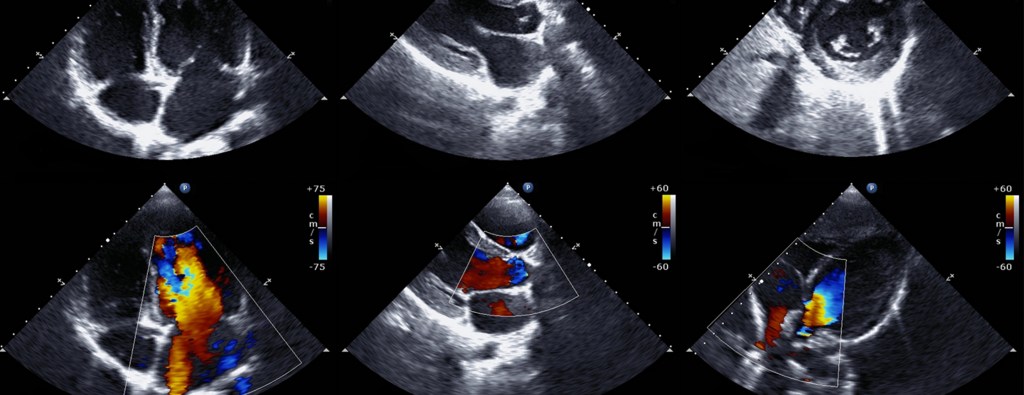

An Echocardiogram (echo) is like an ultrasound, an imaging method that uses sound waves to capture precise images of your heart.

An echocardiogram checks how your heart’s chambers and valves are pumping blood through your heart. An echocardiogram uses electrodes to check your heart rhythm and ultrasound technology to see how blood moves through your heart.